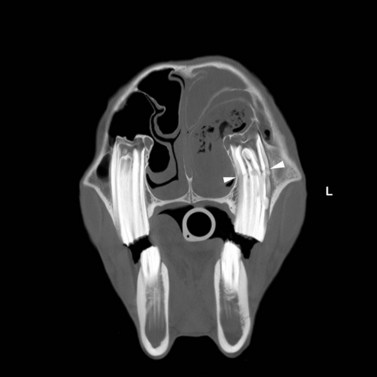

Technical principles

CT is a cross-sectional imaging method that uses a rotating X-ray tube and detector system located in a gantry for image acquisition. When the narrow X-ray beam passes through a selected plane of the body, it is partially absorbed when it passes through tissues with different attenuation coefficients (density). Each tissue is assigned a value that represents its attenuation coefficient. Computerized reconstruction programs are used to assign a gray scale value that correlates to the attenuation value of the tissue being imaged.32 Different algorithms can be used for image reconstructions.33 Each CT instrument manufacturer offers algorithms specifically designed for their individual hardware. For equine dental imaging, a soft tissue algorithm is useful for imaging of the soft tissue structures, followed by a reconstruction in a bone algorithm (high resolution) from the raw data, to allow detailed evaluation of dental and bony structures. The acquired sectional images can be reformatted in various two-dimensional planes or three-dimensional models (Fig. 13.51).

image image

Fig. 13.51 Three-dimensional reconstruction (A) of the bone surface image of an irregular depressed fracture involving the right frontal, nasal, lacrimal, and maxillary bones in a 5-year-old Friesian gelding. The location of fracture lines largely coincides with anatomical suture lines. The distribution and extent of these fractures are well highlighted in the 3D-reformation.